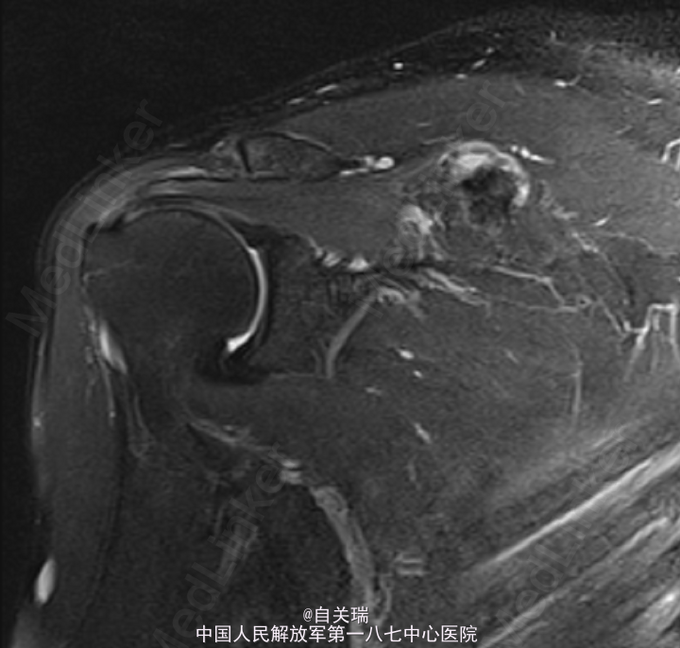

患者,男,49岁,因“反复右肩疼痛1年,发现右肩肿块1周”入院。 患者1年前无明显诱因下右肩部疼痛,无活动不利,无麻木.

右肩胛骨冈上方可触及一肿块,大小约2*3cm,局部压痛(+),皮色皮温正常,右肩活动正常,末梢血供及感觉功能存在。MRI提示:右肩胛冈上缘占位,骨软骨瘤可能。

初步诊断:右肩胛骨肿瘤. 在全麻下行右肩胛骨软骨瘤切除术. 取右肩胛骨沿肩胛冈横行切口,约8cm切口,分离达右肩胛骨见约5*4cm大小,质硬肿瘤组织,与肩胛骨关系紧密,可见软骨帽及纤维膜,予以仔细分离,凿除肿瘤及部分肩胛骨组织.